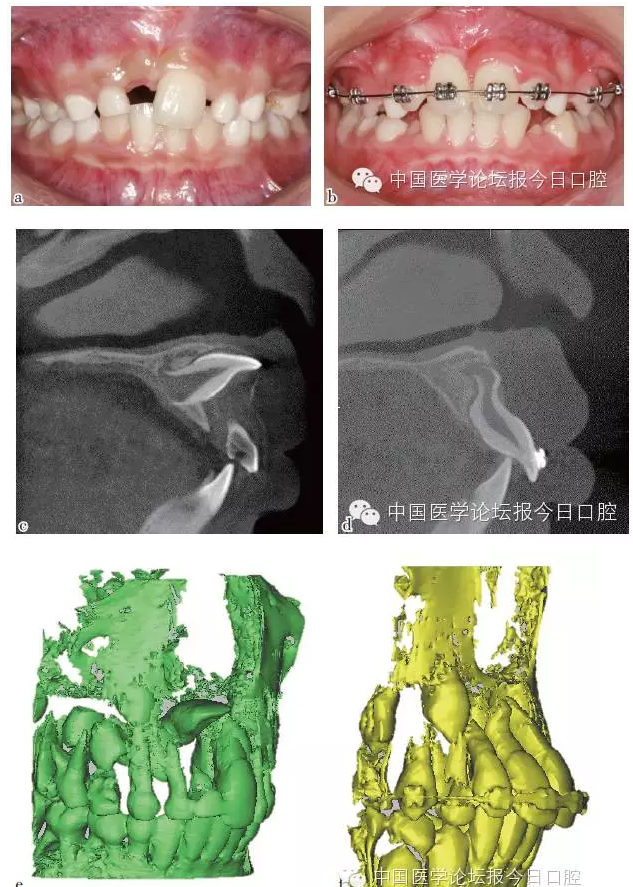

如病例一(圖1)所示,75深齲,34牙胚萌出異常,拔出75,行舌弓間隙維持后,34萌出道自行調(diào)整和萌出。

圖1 75深齲,34牙胚萌出異常,拔除75,舌弓間隙維持后,34萌出道自行調(diào)整萌出

彎根牙的早期牽引助萌

先天及乳牙外傷導致繼承恒牙牙冠及牙根發(fā)育異常,臨床出現(xiàn)牙冠發(fā)育不全及彎根牙。

彎根牙的牽引助萌常受到彎根嚴重程度及彎根角度的影響,早期牽引能引導牙根形成方向,降低牙根彎曲的嚴重程度。

如病例二(圖2)所示,11彎根牙行早期牽引,11牙根繼續(xù)發(fā)育、彎曲程度減小。

圖2 11彎根牙行早期牽引;11牙根繼續(xù)發(fā)育,牙根彎曲程度減小